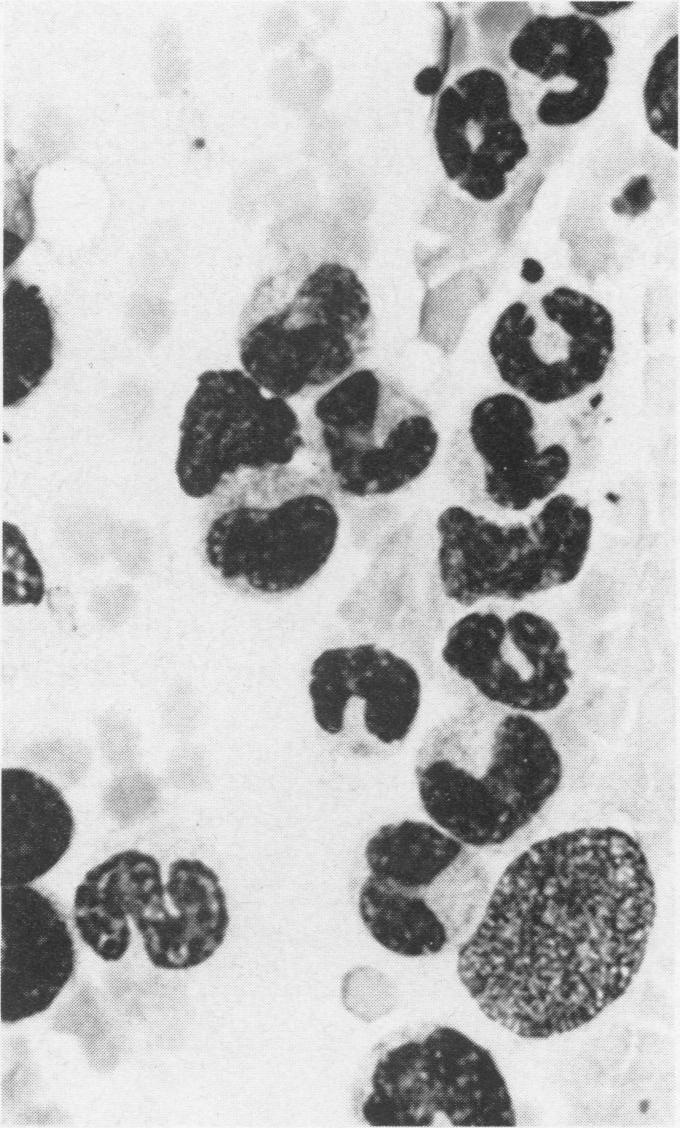

Lambs received T-2 toxin at a rate of 0.6 or 0.3 mg/kg body weight per day in a protein reduced diet for 21 days to study the immunological and pathological effects of T-2 toxin in sheep. Blood was collected before T-2 treatment and on days 7, 14 and 21 of the trial for hematological and biochemical examination and for the separation of peripheral blood lymphocytes for the mitogen assay. Myeloid:erythroid ratios were determined from sternal bone marrow samples taken a day before T-2 treatment began, on day 12 and at death (day 22). Lambs treated with 0.6 mg/kg body weight of T-2 toxin daily were leukopenic on day 7 and lymphopenic on days 7 and 14. Also, on day 7, the mitogenic responses of these lambs to the B-cell mitogen, lipopolysaccharide, were significantly depressed and prothrombin times were prolonged. At necropsy, lymphoid atrophy of mesenteric lymph nodes and spleens was most marked in lambs treated with 0.6 mg/kg body weight of T-2 toxin per day. To the authors' knowledge, this is the first report of leukopenia, lymphopenia and lymphoid depletion in ruminants fed T-2 toxin.